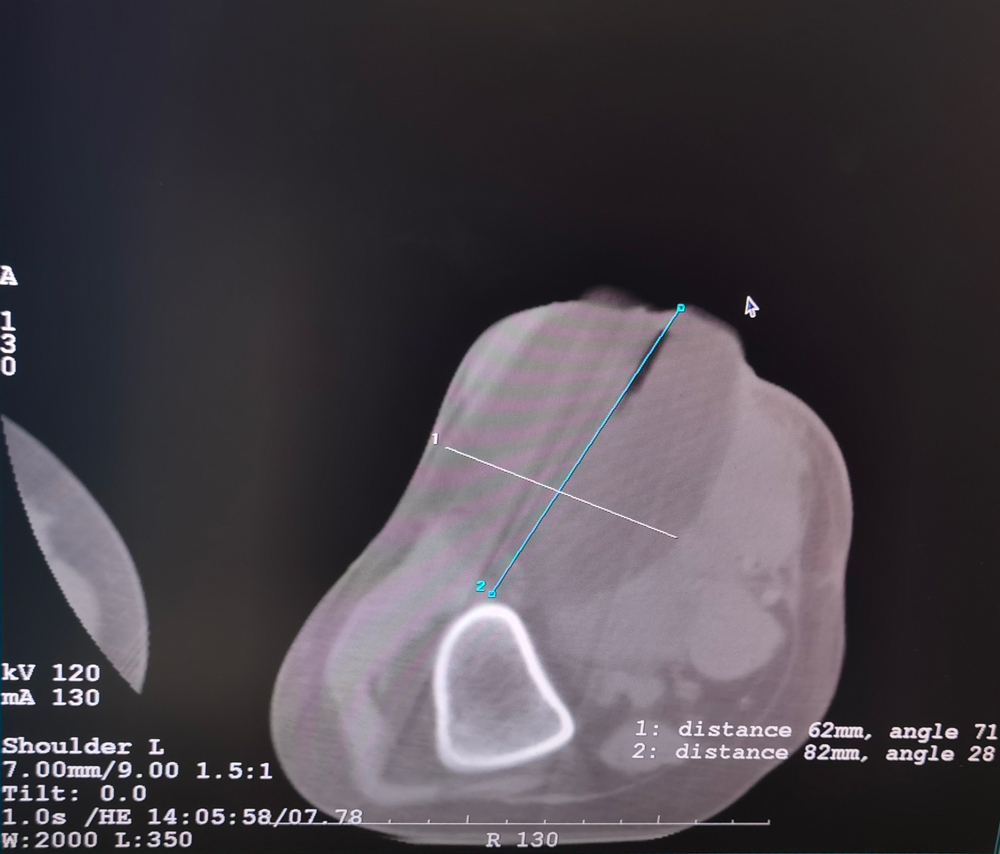

女,56岁,肺转移瘤,骶骨、左侧肋骨各一转移灶,病灶大小均为5cm。骶骨转移灶、肋骨转移灶各进行2个冻融循环。患者术后状况良好。